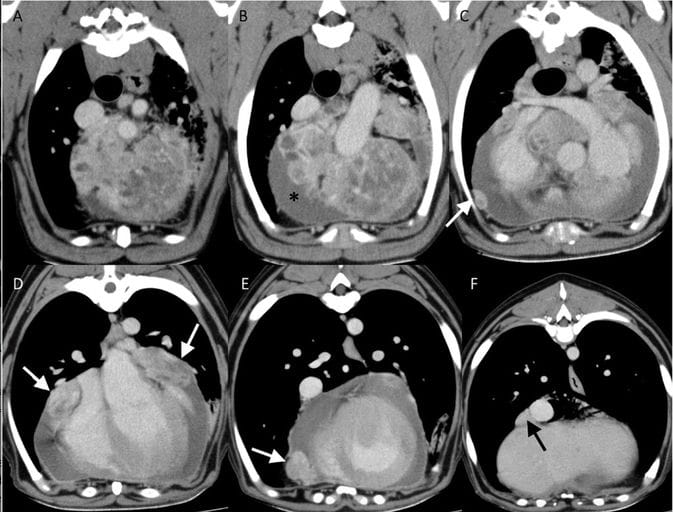

(A–F) Sequential postcontrast transverse CT images (from cranial to caudal) of an ABP with marked pericardial effusion (asterisk) and suspected pericardial (white arrow) and pleural (black arrow) metastases. WW = 352, WL = 62.

All tumors were located at the heart base, typically adjacent to the ascending aorta and pulmonary artery. On CT, masses were generally well-defined, soft-tissue attenuating, and showed moderate to marked contrast enhancement. Mineralization and cystic or necrotic regions were infrequently observed. On MRI, tumors were most commonly iso- to hypointense relative to muscle on T1-weighted images and heterogeneously hyperintense on T2-weighted images, with strong contrast enhancement. Vascular encasement or compression was commonly identified, while direct vascular invasion was less frequent. Metastatic disease was uncommon at the time of imaging.